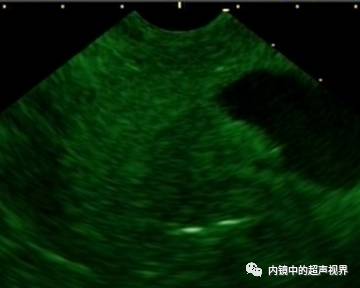

再来一纵隔肿物的图片,是DR30和80的对比,很明显。

纵隔肿物